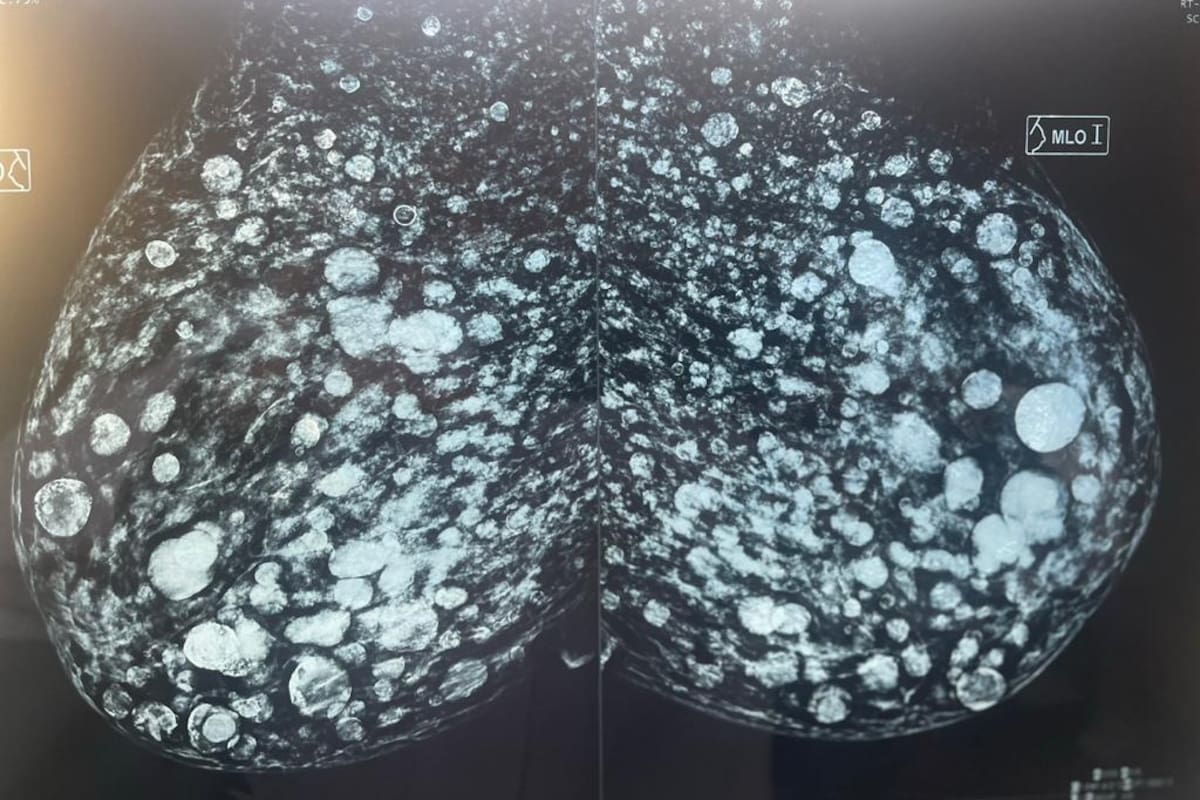

En una mamografía, mostró la “tormenta de nieve” que producen en el tiempo esos productos. “Si una paciente tuviera una lesión sospechosa que pudiera ser cáncer, no lo podríamos ver”, explicó Pedro sobre hasta dónde pueden llegar las consecuencias de procedimientos en los que no se utilizan implantes o productos con garantía de calidad y trazabilidad para bajar costos. “Por el contrario, se trata de productos prohibido, que producen serias secuelas regionales y, en algunos casos, hasta la muerte”.